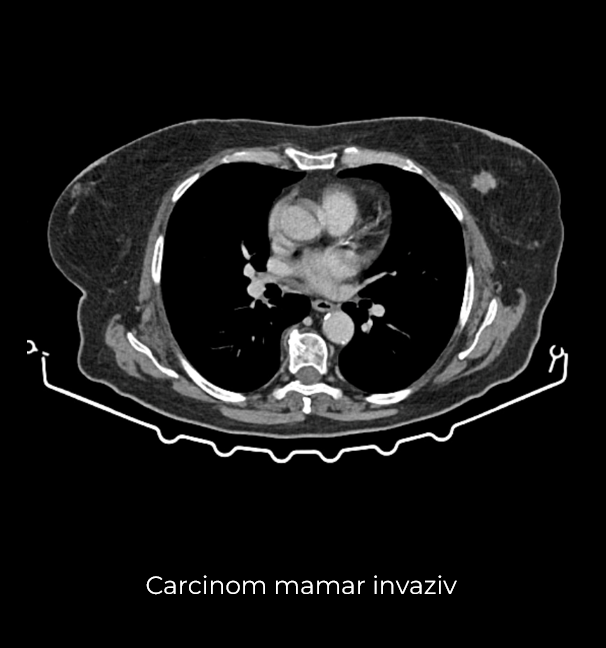

Uneori, o durere aparent banală ascunde în spate o realitate medicală mult mai serioasă. Așa s-a întâmplat și în cazul unei paciente de 63 de ani, care a ajuns la spital pentru dureri pelvine persistente. Investigația CT a schimbat însă complet perspectiva: au fost descoperite trei formațiuni tumorale în zone diferite ale corpului – o tumoră mamară stângă (carcinom mamar invaziv biopsiat), o tumoră pelvi-abdominală voluminoasă (tumoră ovariană) și o formațiune la nivelul peretelui posterior gastric (leiomiom gastric biopsiat).

- Mastectomie radicală stânga – incluzând identificarea și excizia ganglionului santinelă axilar (limfoscintigrafia efectuată în dimineața intervenției a indicat prezența unui singur ganglion santinelă)